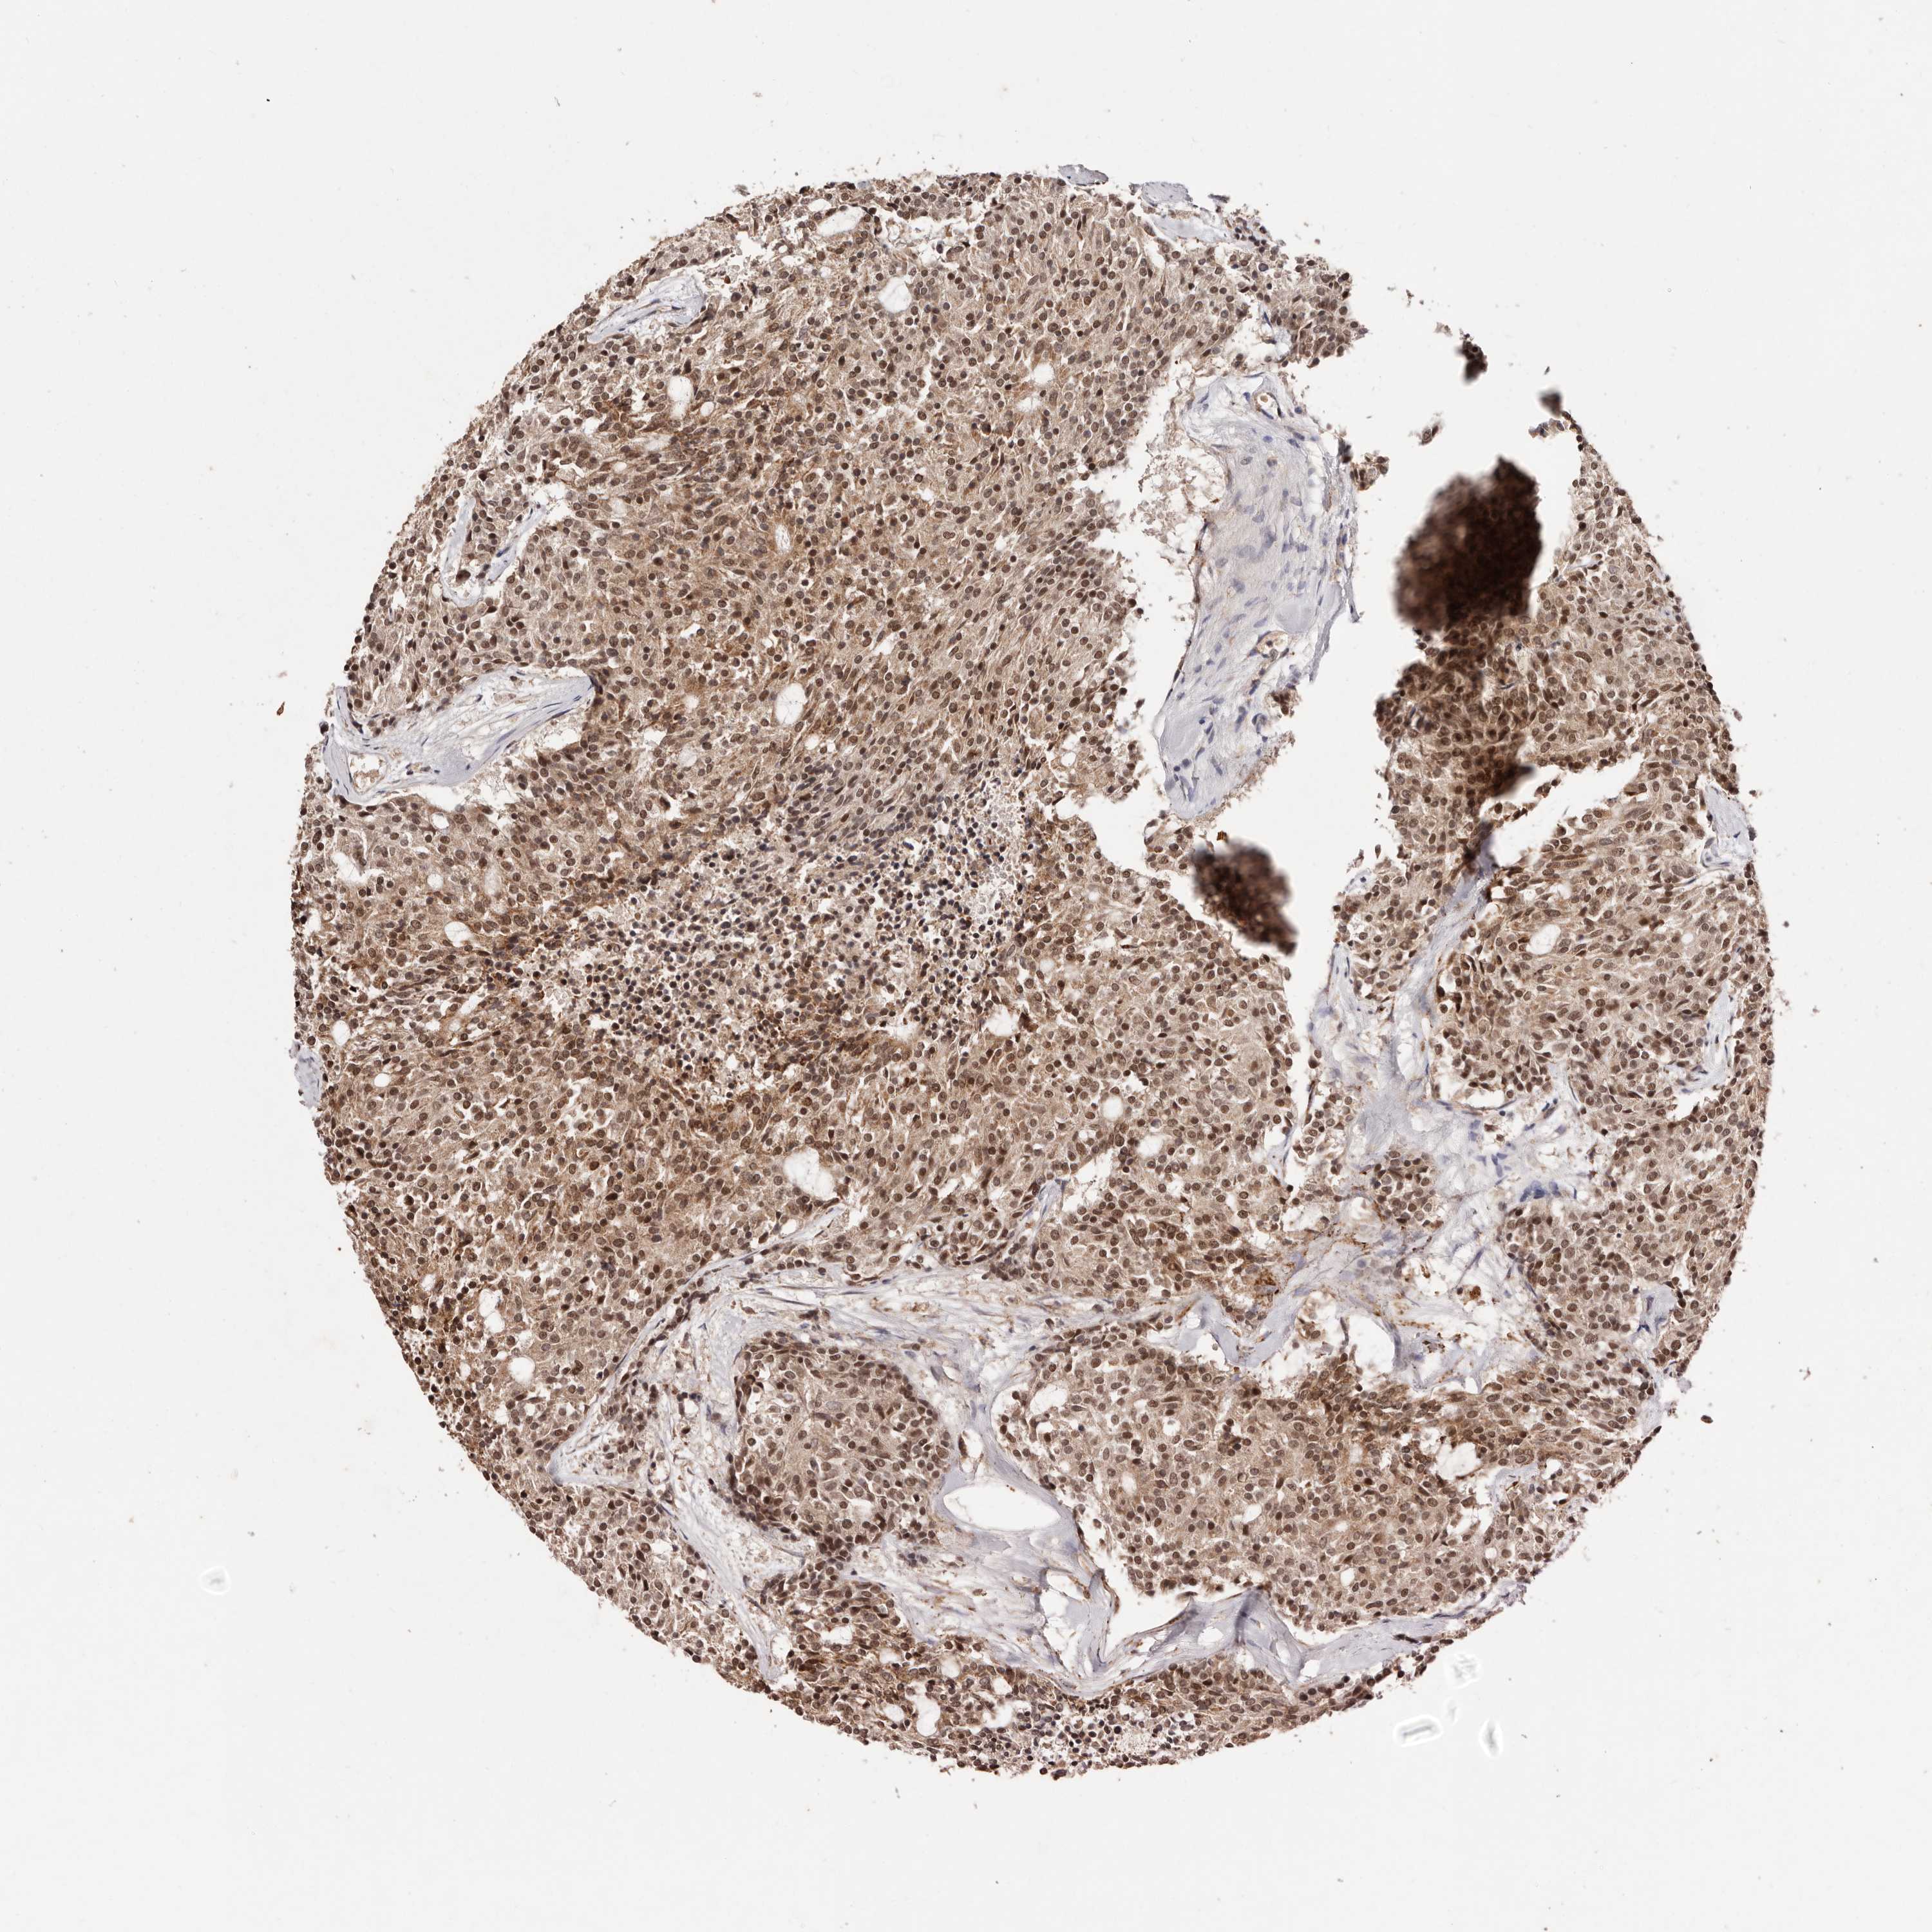

CARCINOID - Protein expressioni

A mouse-over function shows sample information and annotation data. Click on an image to view it in a full screen mode. Samples can be filtered based on level of antibody staining by selecting one or several of the following categories: high, medium, low and not detected. The assay and annotation is described here.

Antibody stainingi

Antibody staining in the annotated cell types in the current human tissue is reported as not detected, low, medium, or high, based on conventional immunohistochemistry profiling in selected tissues. This score is based on the combination of the staining intensity and fraction of stained cells.

Each image is clickable and will lead to virtual microscopy that enables deeper exploration of all samples and also displays staining intensity scores, fraction scores and subcellular localization as well as patient and tissue information for each sample.

Antibody HPA029390

Antibody HPA029391

Staining

High

Medium

Low

Not detected

Intensity

Strong

Moderate

Weak

Negative

Quantity

>75%

75%-25%

<25%

None

Location

Nuclear

Cytoplasmic/membranous

Cytoplasmic/membranous,nuclear

Carcinoid, malignant, NOS

Carcinoma, NOS